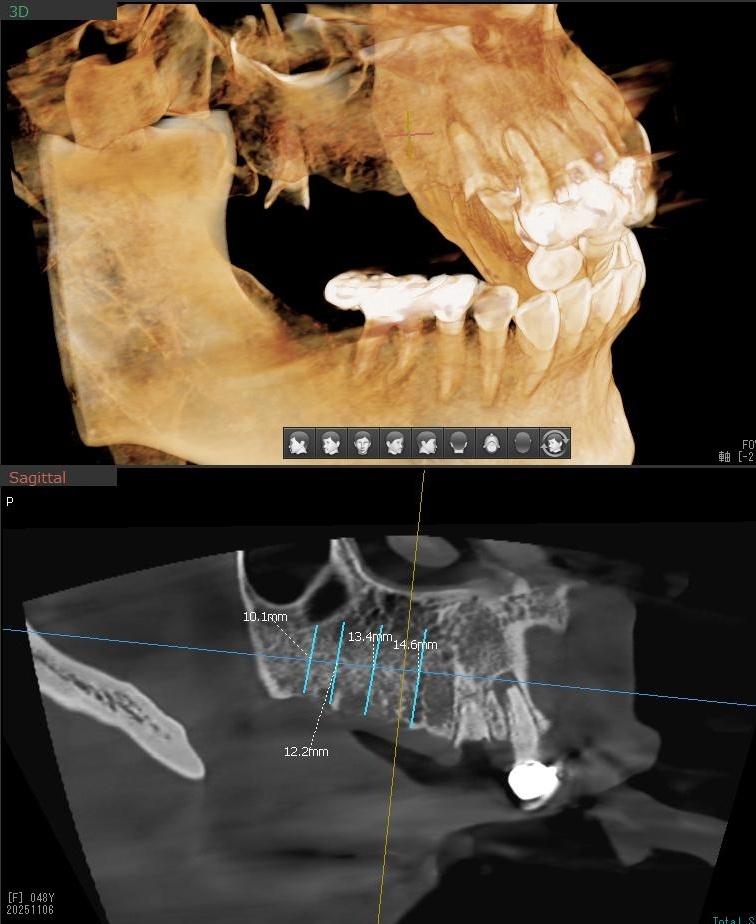

今回の患者様はインプラント植立を希望され、右上4番目・5番目・6番目・7番目の4本の植立が決まりました。